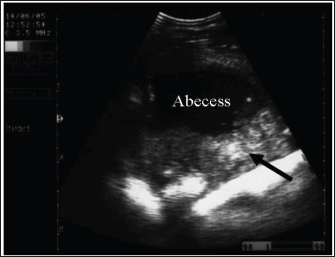

Abdominal abscesses

Intra-abdominal abscessation is not common in adult horses (Aleman et al., 2003; Recknagel et al., 2012) or in foals (Valdes and Johnson, 2005). In a 15-year-study, 40 horses with intra-abdominal masses were studied; 3 of them (7.5%) had mesenteric abscesses (Recknagel et al., 2012). The pathogenesis of abdominal abscessation in horses is presumably similar to that in ruminants (Aleman et al., 2003). It was not possible to determine the cause of the abdominal abscess in the present case. In addition, in equines, the abscess likely formed as a direct extension of a hematogenous infectious process, similar to the development of mesenteric abscess in a bull with chronic peritonitis (Elce, 2006). Several pathogens are considered causative agents of abdominal abscessation, such as Rhodococcus equi, Streptococcus equi subsp. equi, Corynebacterium pseudotuberculosis, Clostridium novyi type A, Blastomyces dermatitidis, and Fusobacterium necrophorum. Pseudomonas aeruginosa can also induce mesenteric abscesses in equines (Arnold et al., 2012; Tharwat et al., 2024c). Equines with abdominal abscesses are usually admitted with a history of fever, weight loss, colic, inappetence, and signs of depression of various durations (Tharwat et al., 2024c).

Abdominal abscess was strongly suspected on the basis of ultrasonographic findings (Fig. 20). The differential diagnoses include abdominal neoplasia. Ultrasonography is also useful for percutaneous needle aspiration for bacteriologic evaluation and facilitates intralesional antibiotic treatment and drainage because the thick abscess capsule prevents the spread of antibiotics (Tharwat et al., 2024c) (Figs. 21 and 22). For large abscesses, transcutaneous aspiration of pus should be performed under ultrasound guidance, as reported in cattle (Mohamed et al., 2002; Mohamed et al., 2003a,b,c; Mohamed and Oikawa, 2008). The ultrasound-guided percutaneous drainage of abdominal abscesses has several advantages. First, the animal should not be anesthetized. Second, surgery is not required, and consequently postoperative drawbacks will not develop. Third, percutaneous drainage is typically cost-effective. Fourth, percutaneous ultrasound-guided drainage can be performed promptly after diagnostic ultrasound is performed because the methodology does not require any particular planning or preparation and can be completed quickly if the examiner is experienced. Complications associated with ultrasound-guided percutaneous aspiration of the abscess in the present case were not encountered (Tharwat et al., 2024c). Follow-up after pus aspiration confirmed the treatment response, reduction in abscess size, and recovery (Figs. 23 and 24).